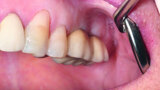

Fig. 14: Preoperative intraoral finding in the atrophic posterior mandible.

Fig. 15: Combination of full- and partial-thickness flap elevation.